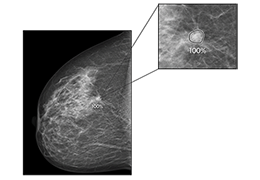

成像智能。

Eclipse 成像智能功能提供强大的处理能力和最佳质量的影像,同时减少质量错误并提高剂量效率。

凭借 AI、专有算法和先进的影像处理能力,提供出色的影像质量和无与伦比的诊断信心。